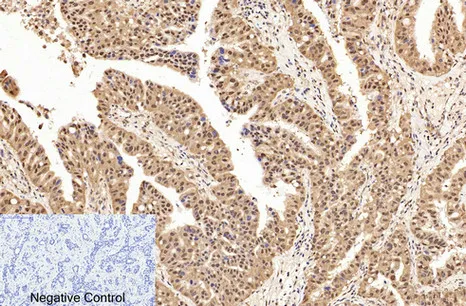

Caspase-7 Rabbit Polyclonal Antibody

Cat: APRab07980

CD19 Rabbit Polyclonal Antibody

Cat: APRab08256